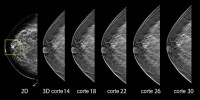

Medico radiólogo / mastología en Cancún especializada en diagnóstico de patología mamaria y pesquisa de cáncer de mama. Ultrasonido, Biopsias, Radiolocalizaciones, control de mama, mastografía, estereotaxia y más con mas de 15 años de experiencia.